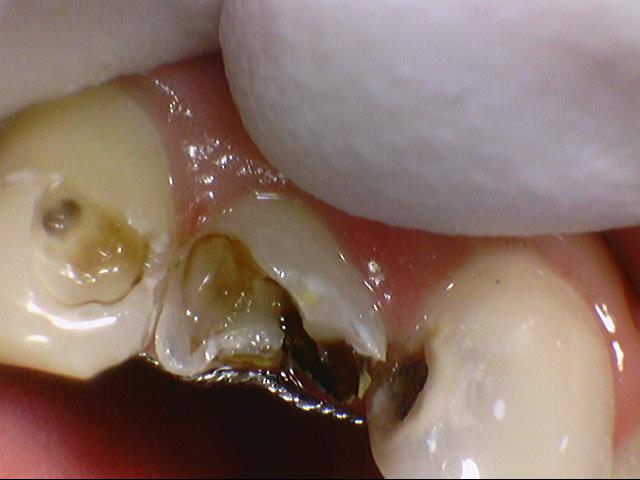

위의 사진에서 철사보이시죠?

이렇게 교정 유지장치가 붙어있는데 많이 썩은 치아에서

환자분이 유지장치를 떼기 싫어하셔서

라미네이트로 치료를 마무리 하였습니다.

화살표된 두개 앞니 치아 치료